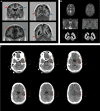

The genetic etiology of intellectual disability remains elusive in almost half of all affected individuals. Within the Solve-RD consortium, systematic re-analysis of whole exome sequencing (WES) data from unresolved cases with (syndromic) intellectual disability (n = 1,472 probands) was performed. This re-analysis included variant calling of mitochondrial DNA (mtDNA) variants, although mtDNA is not specifically targeted in WES. We identified a functionally relevant mtDNA variant in MT-TL1 (NC_012920.1:m.3291T > C; NC_012920.1:n.62T > C), at a heteroplasmy level of 22% in whole blood, in a 23-year-old male with severe intellectual disability, epilepsy, episodic headaches with emesis, spastic tetraparesis, brain abnormalities, and feeding difficulties. Targeted validation in blood and urine supported pathogenicity, with heteroplasmy levels of 23% and 58% in index, and 4% and 17% in mother, respectively. Interestingly, not all phenotypic features observed in the index have been previously linked to this MT-TL1 variant, suggesting either broadening of the m.3291T > C-associated phenotype, or presence of a co-occurring disorder. Hence, our case highlights the importance of underappreciated mtDNA variants identifiable from WES data, especially for cases with atypical mitochondrial phenotypes and their relatives in the maternal line.